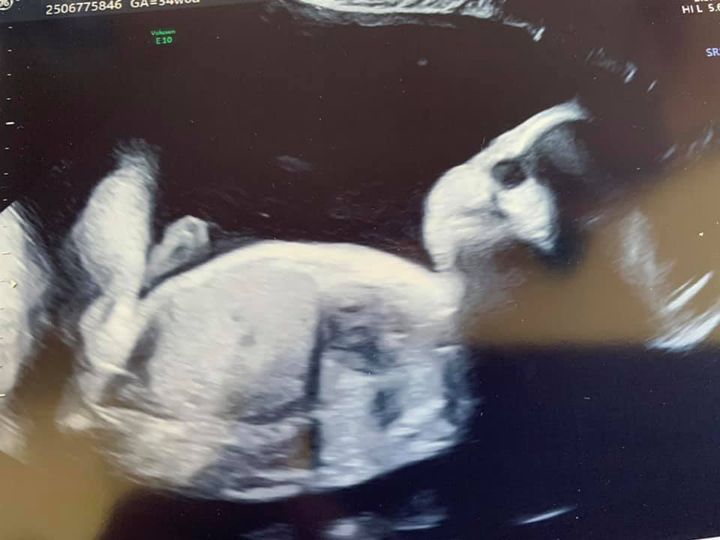

and a final appointment with my paediatrician… a new choice is I’ve now requested intubation at birth if needed. Something I was originally going to avoid on the basis of her diagnosis but because of some positives in scans and because of my endless research into Trisomy 18 I now believe she has a reasonable chance of life (how long for is unknown) and I want to ensure she is fully assessed and not judged simply on the basis of her diagnosis. Martin McCaffrey also told me if she makes it past 1 month we have a 40% chance of survival past her 1st birthday.. I realise that must sound horrific to you all but I have gone through this pregnancy believing she only had a 5-10% chance of this so I’m clinging to hope.. it is all I have at this point.So to Ambers scan.. my fluid levels has gone up high this week … not great but hopefully will cause no problems. Her heartbeat

is strong! Cord flow good and her weight… has gone up!! My baby girl is now estimated at 5lbs3oz which is INCREDIBLE for a Trisomy 18 baby!! Just over a whole lb more than last week! (that’s bigger than mum said said my sister Wendy was!! ![]()

) And.. I don’t know how much to read into this but Ambers hand was OPEN! To explain the excitement of this you need to understand that Trisomy 18 babies usually have clenched fists as Amber has had at all her scans so far.. this is a signifier of neurological/brain issues … so for her hand to be open is maybe a good sign?? I’ll be speaking to my paediatrician tomorrow and asking her opinion

Photos from today

Ambers tiny open hand and face and also a gorgeous photo of the wee jacket and bonnet my mum has knitted for Amber.. ready to pack in my hospital bag ![]()